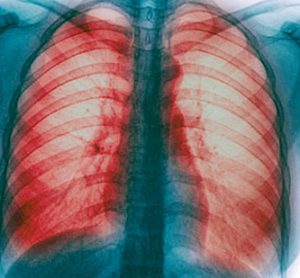

Afatinib significantly improved clinical outcomes compared to gefitinib in NSCLC trial

Results from the Phase IIb LUX-Lung 7 trial showed that afatinib significantly reduced the risk of lung cancer progression by 27% versus gefitinib...